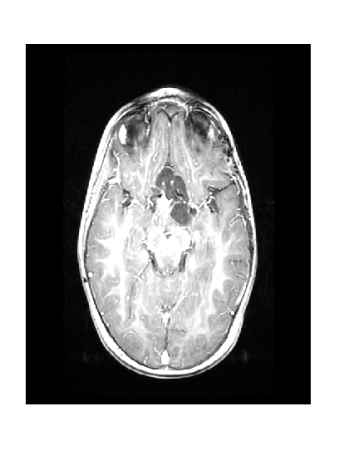

Figure 3 displays the reconstruction MSNR for the various test cases as cataloged in Table 1. Figures 1 and 2 display some examples of reconstructed images for cases of interest.

Due to its wide use in image processing, we consider the use of gradient sparsification with LACS-MRI. We show below that it is possible to produce image reconstructions with significantly higher Reconstruction SNR using gradient sparsification. We have repeated some of the simulations from above for different compression levels, , using the gradient transform to sparsify instead of the wavelet transform. We will refer to this as ”LACS-MRI with gradient sparsity.” We compared the performance of each sparsification method at each compression level using LACS-MRI and then compared this to the L1-W method. Again, we use a reference image and a follow-up image that we hope to recover as in Figure 8. We consider here only the phantom image, as it serves as a prime candidate for gradient sparsification, and is small enough that evaluation of all PDFs is computationally feasible.

Figure 12 shows the effect of a 2-fold scale difference on LACS-MRI image reconstructions. There are extensive streaking artifacts and significant detail is lost compared to the ground truth and the reconstruction using the modified method. Clearly, the Grayscale Compensation for Reference Based MRI Algorithm (GSC) can reduce these artifacts and help improve the visibility of structure.